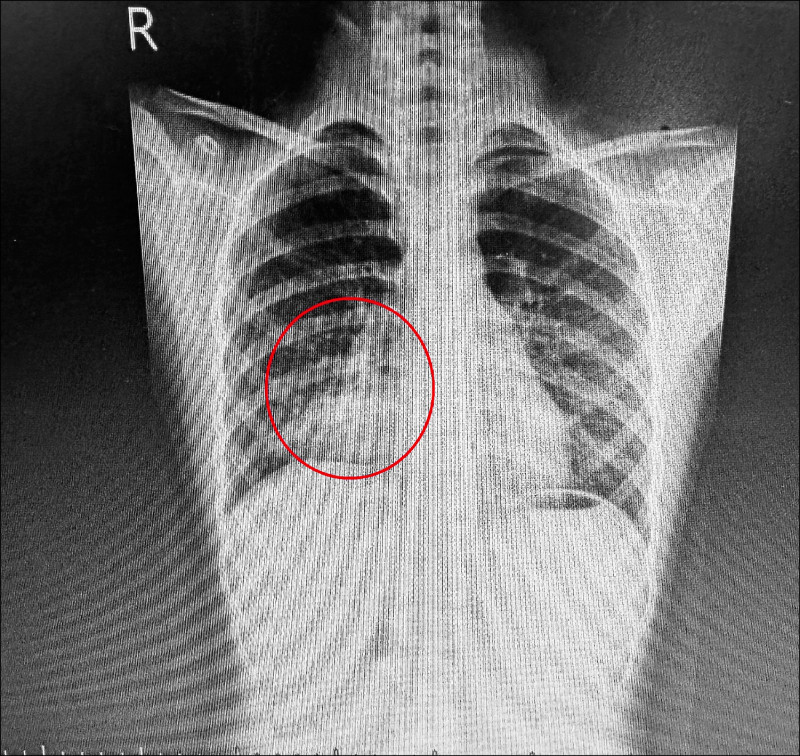

賴永清說,黴漿菌肺炎引發的非典型呼吸道感染,常讓患者即使發燒,仍保有活力,被稱為「行走肺炎」。根據患者胸部X光檢查顯示為右下肺葉肺炎,且血液檢驗查出白血球數等多項感染指數上升,表示有明顯細菌性感染,泌尿道也受到感染,進一步檢驗發現,黴漿菌抗體濃度高達128倍,正常值應小於16倍,推估黴漿菌感染至少持續4週以上。